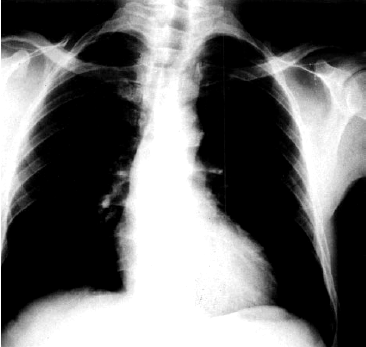

Длительное время в период компенсации порока размеры сердца почти не изменены, что объясняется отсутствием заметной дилатации ЛЖ. При декомпенсации сердца и развитии миогенной дилатации желудочка наблюдаются типичные рентгенологические признаки его расширения (см. выше), в частности удлинение нижней дуги левого контура сердца. При значительном смещении верхушки влево угол между сосудистым пучком и контуром ЛЖ становится менее тупым, а “талия” сердца — более подчеркнутой. Такая конфигурация сердца получила название “аортальной”, так как наиболее отчетливо проявляется при аортальных пороках сердца (недостаточности клапана аорты и стенозе устья аорты в стадии декомпенсации).

Кроме того, выраженное сужение устья аорты нередко приводит к постстенотическому расширению аорты, что объясняется значительным увеличением скорости систолического потока крови через суженное аортальное отверстие и высоким давлением струи крови на стенку аорты (рис. 8.50).

| Рис. 8.50. Рентгенограмма сердца в прямой проекции больного с аортальным стенозом. Заметно увеличение левого контура сердца с подчеркнутой "талией" сердца (аортальная конфигурация) и постстенотическое расширение аорты |